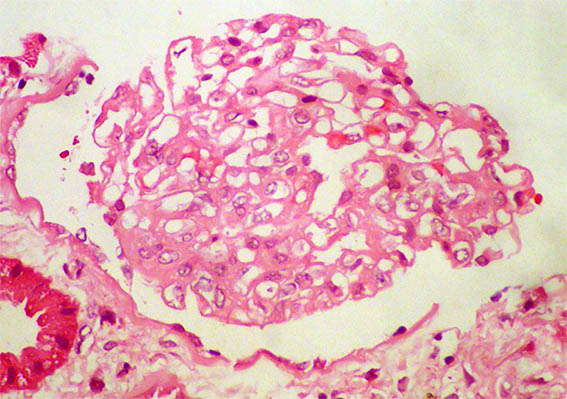

Figure 2. H&E, X400. Acute tubular damage.